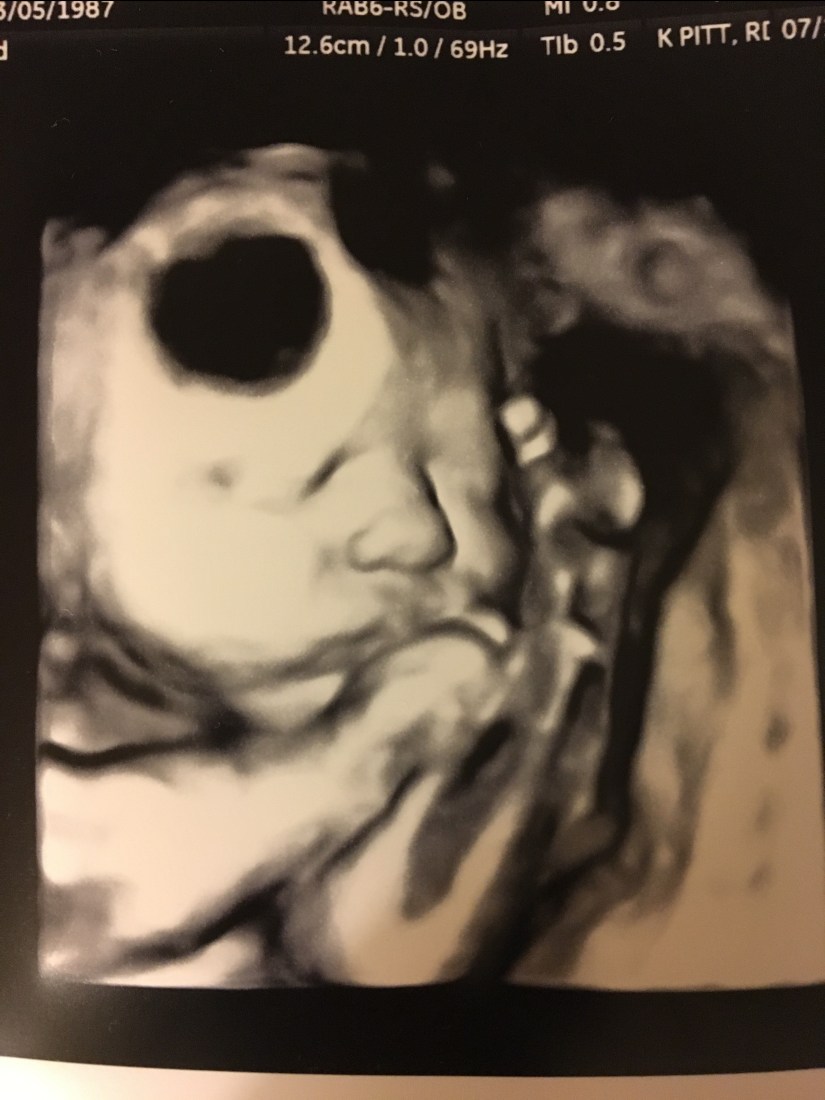

Now- on to the actual doctor appointment update! The fun part! We went today and FINALLY got another ultrasound- the one thing I can thank diabetes for! However, we learned that this dear baby inside of me potentially weighs 6 POUNDS, 3 OUNCES! Um, hello- that is infant- sized for some full-term babies- and this one in me still has 4-5 weeks to go! That is almost HALF of the weight I have gained period from this pregnancy! She also has a longer thigh bone, so she could potentially be a taller baby! Have you met Will and I? Or our families?! None of us are tall…so that’s funny! Her belly is definitely a little rotund as well. She was not a fan of having her picture taken today- but our awesome ultrasound tech- Kelly, was still able to get us some good pictures!

Those are not holes in her head, or weird skin places- she had her face squished up next to the placenta, which makes it hard for the camera to get a good angle to actually show everything!